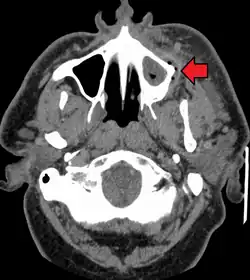

Dental caries can also cause bad breath and foul tastes.[16] In highly progressed cases, an infection can spread from the tooth to the surrounding soft tissues. Complications such as cavernous sinus thrombosis and Ludwig angina can be life-threatening.[17][18][19]